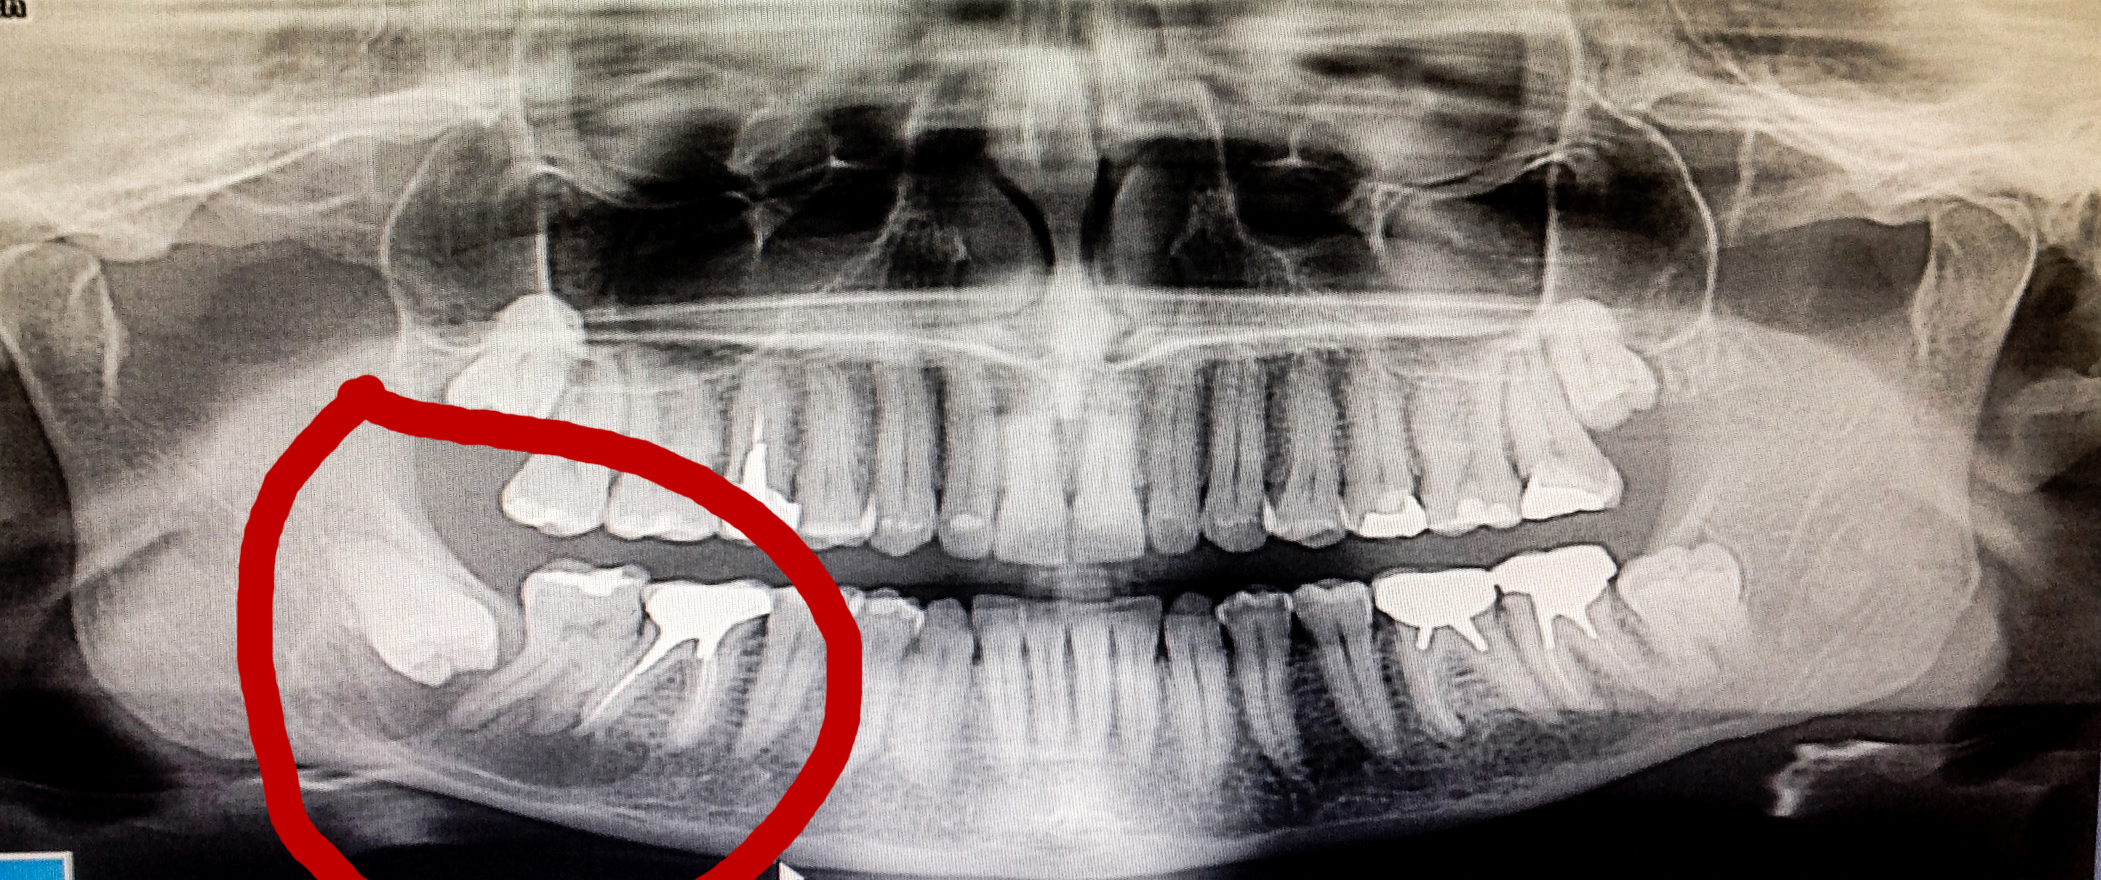

buongiorno. Vorrei un opinione. E' da circa un anno e mezzo che sento come "qualcosa" sotto un dente. Lo scorso anno ho fatto una radiografia e sembrava tutto apposto. E' però da una settimana che sento come un formicolio o strana sensazione alla lingua, oggi per precauzione ho fatto un'altra radiografia ed è saltata fuori una ciste abbastanza grande. Ho allegato la foto. E' una foto che ho fatto con l'ipad al monitor del dentista, ma si vede chiaramente la ciste sotto tre denti. Fino a qualche ora fa, nemmeno sapevo dell'esistenza di cisti sotto i denti. Adesso lo so, perchè ce l'ho! Io oggi sono andato da un dentista "a caso" solo per fare la radiografia, ma io vivo all'estero (in Giappone) e quindi l'asportazione, la farò probabilmente in Giappone. Vorrei comunque qualche rassicurazione, capita solo a me? Rischio di morire? Rischio di perdere la sensibilità della bocca? ... il dentista ha detto che nonostante sia molto grande, è lontana dai nervi e quindi dovrebbe essere un intervento di routine! Mi toglieranno tutti e tre i denti? Dente del giudizio e i due denti vicini? ... solo con anestesia o mi addormenteranno? Io vivo in Giappone, ma non parlo giapponese. Ci sarà mia moglie giapponese a tradurre, ma vorrei sapere i rischi che corro a fare questa operazione. Devo dire di avere molta paura, e se invece di una ciste fosse un tumore maligno? ... lo so che si può sapere solo con un esame istologico, ma avendo avuto questa notizia da qualche ora, sto cercando di capire la gravità della situazione. Sempre e solo guardando la radiografia, potrebbe esistere un modo per aspostarla senza togliere i tre denti? ... scusate le molte domande. Essendo un residente all'estero, in Italia non ho la sanità e quindi non essendo in un'ottima situazione economica, farò questo in Giappone dove pago ogni mese l'assicurazione nazionale. Ultima domanda, se si facesse in Italia, sarebbe meglio farlo fare in un ospedale o in un centro odontoiatrico? O sarebbe la stessa cosa? ... sono di Bergamo Grazie

Caro Signor Adamo, Buongiorno. Legga nelle due ultime risposte precedenti l'importanza di una Rx Endorale, per l'osteolisi periapicale che ha. Per il dente del giudizio incluso invece va bene la OPT che ha postato. E' da circa un anno e mezzo che sento come "qualcosa" sotto un dente. "Lo scorso anno ho fatto una radiografia e sembrava tutto apposto". Assurdo stare con questi sintomi descritti così a lungo senza andare dal Dentista. Ancora più assurdo è dire , dopo Visita Clinica e radiologica che "andava tutto a posto". La nuova OPT postata mostra un Dente del Giudizio incluso con stretti rapporti con il canale mandibolare inferiore, dove transita il nervo alveolare inferiore e la osteolisi periapicale della radice mesiale del secondo molare e distale del primo è talmente vasta che sicuramente c'era , magari solo in forma iniziale anche nella prima lastra, o almeno ci sarebbero dovuti essere segni radiologici indiretti di sofferenza periradicolare e peri alveolari inferiori coi relativi sintomi di parestesie per questi ultimi e di risposta agli stimoli termici per le osteolisi e le relative sofferenze pulpari, sempre che non si tratti di una osteolisi non odontogena che è la prima diagnosi differenziale da fare! Esistono infatti Osteilisi odontogene e osteolisi non odontogene. La Grande Assente, come al solito, dicevo, è proprio la Diagnosi che è la conseguenza di una Visita Odontoiatrica Accurata e che impegna Dentista e Paziente per tanto tempo! Non basta un'occhiata e via! Non Bisogna valutare solo il Dente in questione ma analizzare tutto l'apparato Stomatognatico, Gnatologicamente, Parodontalmente, Conservativamente, Funzionalmente, Esteticamente. Tutto questo, senza estrapolare la "bocca" dal contesto dell'Organismo intero in cui si trova che va valutato quindi insieme alla "bocca", Clinicamente, Anamnesticamente, Semeiologicamente per fare Diagnosi Differenziali che Nascono Solo dalla conoscenza delle varie patologie ed emettere infine un sospetto Diagnostico che diventa poi Diagnosi Certa con "Ragionamento Clinico e Strumentale e eventualmente analitico ematologico". Si emette così una Prognosi ed infine la Terapia ed ho detto "La", non "Una" Terapia che sceglie il Dentista e solo il Dentista!Le posso fare solo un Discorso Generale e come mi comporterei io in una simile situazione! Di fronte ad un dolore come quello da lei descritto, bisogna valutare la Vitalità dei denti e se c'è una iperemia passiva da danno venoso che non è altro che una pulpite, non è reversibile e bisogna procedere alla terapia endodontica, se fosse una iperemia attiva con danno arterioso, la sofferenza pulpare sarebbe reversibile! Se il dente fosse positivamente normale allo stimolo freddo, bisogna portare su esso uno stimolo caldo per valutare la presenza di una sintomatologia radicolare della polpa! Le spiego meglio: il dolore è dovuto semplicemente ad un maggior afflusso di sangue nel dente tramite l'arteria che lo porta, dovuto ad un meccanismo di difesa nei confronti dello stimolo irritativo, questo maggior afflusso causa una pressione dentro il dente che è inespansibile e comprime le terminazioni nervose causando dolore esacerbato dallo stringere i denti o dal "picchiettarvi sopra" o dagli stimoli termici in questo caso (che si chiama iperemia attiva) il processo è reversibile, la polpa si abitua ed in qualche giorno o settimana tutto scompare, se invece il danno causato dalle tossine dei microbi continua si ha una alterazione della vena che fa uscire il sangue dal dente e succede che il sangue arriva con l'arteria e non esce più con la vena danneggiata, si ha pressione che può anche scatenare dolori forti formando la cosiddetta pulpite acuta o essere talmente leggera da non causare dolori in questo caso anche molto lenta, formando una pulpite cronica o meglio cronicizzata e le cellule della polpa del dente, arterie, vene, linfatici e tessuto nervoso, se non curata, muoiono ossia vanno in necrosi e si può formare una zona di osteolisi periapicale (pallina nera alla Rx) intorno all'apice della radice, ossia un granuloma, cisti. Poi una visita Gnatologica e conservativo-endodontica accurata ed una visita Parodontale e una visita o almeno una anamnesi ed una semeiologia sistemica e stia certa che si arriva ad una diagnosi. Tenga inoltre presente che la visita Odontoiatrica deve essere totale. Legga, nel mio Profilo "Visita Parodontale" che poi è la Visita Odontoiatrica che io Parodontologo ma anche Odontoiatra ed anche Medico faccio sempre, così come mia figlia Claudia, per qualsiasi motivo un paziente venga da noi! Eventualmente richiedere analisi ematologiche in cui Ves e PCR mosse verso l'alto possono indicare la presenza di infezioni pericolose per le Malattie Focali. Dovrebbe completare le analisi col titolo ASLO e RA Test oltre che Emocromo con Formula, se sospettassi una Malattia Focale. Riguardo alla sua ultima domanda se la si possa "asportare" senza l'avulsione (estrazione) dei denti, bisogna per prima cosa stabilire che sia odontogena. In questo caso, basta curare endodonticamente il secondo molare se fosse in necrosi e quindi Vivo e non Vitale ed eventualmente ritrattare il primo molare endodonticamente. Le spiego: Concettualmente i microbi presenti nella radice inviano fuori nell'osso le loro tossine a cui l'organismo risponde con la formazione cistica o granulomatosa per arginare l'infezione stessa e difendersi, e i corpi dei leucociti macrofagi che arrivano in massa, formano il pus. Tolti i microbi con la terapia endodontica per via ortograda (normale ) o retrograda, se fossero presenti ostacoli insormontabili come perni non rimovibili etc (chirurgica) le tossine non vengono più emesse e la zona di osteolisi (lisi dell'osso) scompare con rigenerazione dell'osso stesso. Se fosse una cisti non odontogena, rara in questa zona, ma da prendere sempre in considerazione, si può fare un intervento chirurgico di "Cistectomia" senza estrarre i denti e senza ledere il Nervo alveolare inferiore che transita, come detto, nel Canale Mandibolare. Questo in linea di massima, non avendola Visitata!!! Spero di esserle stato utile ed esaustivo. Cari saluti

Sig. Adamo, con tutti i limiti diagnostici che la sua radiografia presenta, ( una panoramica non è mai sufficiente a dare una rappresentazione precisa del caso.) mi sentirei di dirle di non lasciarsi prendere da ansia eccessiva. La osteolisi c'è, senza dubbio, ma mi sembra che sia in connessione con le radici dei 2 molari presenti: mi sentirei di dire che una analisi radiografica mirata e la analisi di vitalità sul 7ttimo e una revisione del trattamento canalare del 6esto, dovrebbero risolvere il suo problema preservando i sui 2 molari. Il livello di competenza odontoiatrica in giappone è molto elevato ! Auguri.

Ceco di risponderle brevemente ed in maniera chiara. La panoramica è un esame preliminare, servono radiografie endorali mirate e specifiche ed anche una Tac Dentale o CBCT a scopi diagnostici e pre - operatori (necessaria quest'ultima per valutare effettiva estensione e localizzazione della cisti, e suo rapporto con il canale mandibolare). Premesso che non si muore nè al 99% si tratta di una neoplasia maligna, bensì di una cisti odontogena (follicolare o radicolare che sia, ma sempre benigna è, anche se comunque verrà biopsiata una volta asportata per sicurezza) non si tratta neanche di un intervento e di una pianificazione terapeutica da prendere sotto gamba. Opportuno rivedere la terapia canalare del 46 e valutare vitalità del 47 (spesso in questi casi si devitalizza, ma non sempre), ovviamente estrarre l'ottavo in evidente disodontiasi e rimuovere la cisti. Quindi è necessaria una diagnosi certa eseguita con gli esami diretti ed indiretti adeguati, un piano di trattamento corretto e uno studio dove collaborino un Chirurgo Orale ed un Dentista esperto in Endodonzia (bravissimi i chirurghi nelle strutture oubbliche ripo Maxillo - Facciale, ma spesso poco conservativi sui denti residui). In ogni caso in Giappone l'Odontoiatria è ad alti livelli, e quindi non dovrebbe avere problemi in tal senso.

Gentile Sig. Adamo, sicuramente la lesione stà comprimendo il nervo alveolare inferiore. Il 48 è da estrarre, il 47 da valutare attentamente e il 46 da ritrattare. Sicuramente chiederei una CBCT per confermare il mio sospetto. Cordiali saluti

Gentile sig. Adamo, la lesione sembrerebbe collegata a problemi endodontici a carico dei molari (forse solo di quello già trattato). facendolo ritrattare da un bravo endodontista potrebbe guarire SENZA DOVER ESEGUIRE INTERVENTI CHIRURGICI, che potrebbero portare a una perdita di sensibilità del suo labbro. sul sito della SIE (società italiana di endodonzia) troverà molti endodontisti di esperienza che potrebbero evitarle un intervento problematico. in alternativa, una volta appurato che il 47 è vitale, anche la semplice estrazione del 46, senza dover "scavare particolarmente" potrebbe essere risolutiva. ovvio che, affinché il suo osso si riformi, occorreranno diversi mesi, ma alla fine, tolta la causa, il problema guarisce. al contrario se nell'intervento il suo nervo alveolare viene danneggiato, il danno può essere permanente. anche in Giappone ci sono bravi endodontisti, ma non so se le cure erogate da strutture pubbliche siano o meno di buon livello. domo arigatò :-)

Sig adamo, certamente il cosi detto dente del giudizio (48) è da estrarre, ritengo anche il 47, il 46 si può salvare facendo un ritrattamento endodontico, la cisti è da eliminare; il tutto va fatto da un buon chirurgo che abbia una struttura ben organizzata e attrezzata .